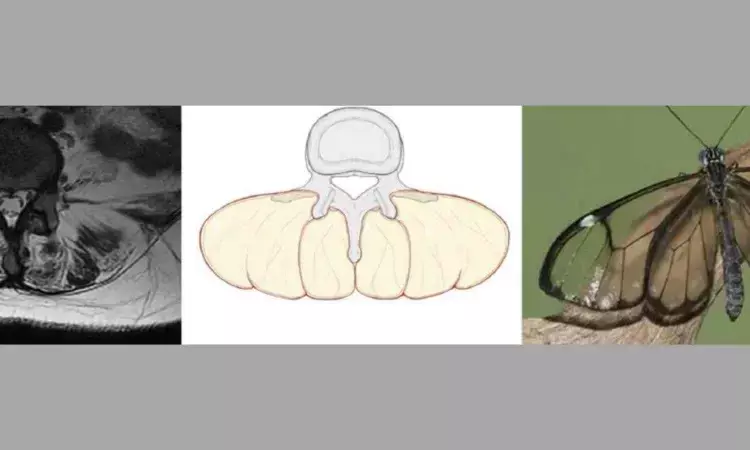

Muscle atrophy and fat infiltration result in extensive fat deposits in the posterior paraspinal muscles, which, when viewed on T2 axial MRI along with the vertebral body and spinous processes, produces a distinctive imaging appearance similar to that of a glassy-winged butterfly (Greta oto), which can be referred to as the “Greta oto” sign.

There were three females and one male, aged from 38 to 55 years. MRI examinations showed significant atrophy and fat infiltration of the bilateral erector spinae muscles, as well as varying degrees of atrophy observed in the multifidus muscles. The fatty degeneration in the erector spinae and multifidus muscles, together with the vertebral bodies and spinous processes, produced a distinctive imaging manifestation resembling a “Greta oto” sign on axial T2-weighted MRI scans in all patients. Ultimately, all four patients were referred to the neurology department, where the diagnosis of myopathy was confirmed by muscle biopsy (one myopathy with early-onset Paget disease and frontotemporal dementia type 1 (IBMPFD), one HMGCR antibody-positive myopathy, one myotonic dystrophy and one limb-girdle muscular dystrophy.